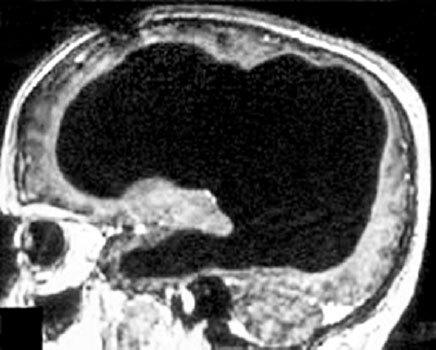

МРТ-снимок мозга, демонстрирующий отсутствие около 90 % нервной ткани (сплошное затемнение). Черепная коробка мужчины в основном заполнена жидкостью.

Подробное описание его случая вместе с МРТ-снимками мозга было опубликовано в самом авторитетном медицинском журнале Европы Lancet в 2007 году и до сих пор поражает научное сообщество[11].